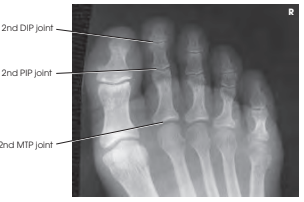

Structures shown

이 촬영법으로 얻는 영상은 발가락 14개의 골격과 발등뼈(metatarsals)의 원위부를 포함합니다. AP Axial 투사에서는 IP 관절과 MTP 관절 공간을 열어 보여줍니다.

- IP 및 MTP 관절 공간이 AP Axial 투사에서 잘 열려 보여야 합니다.